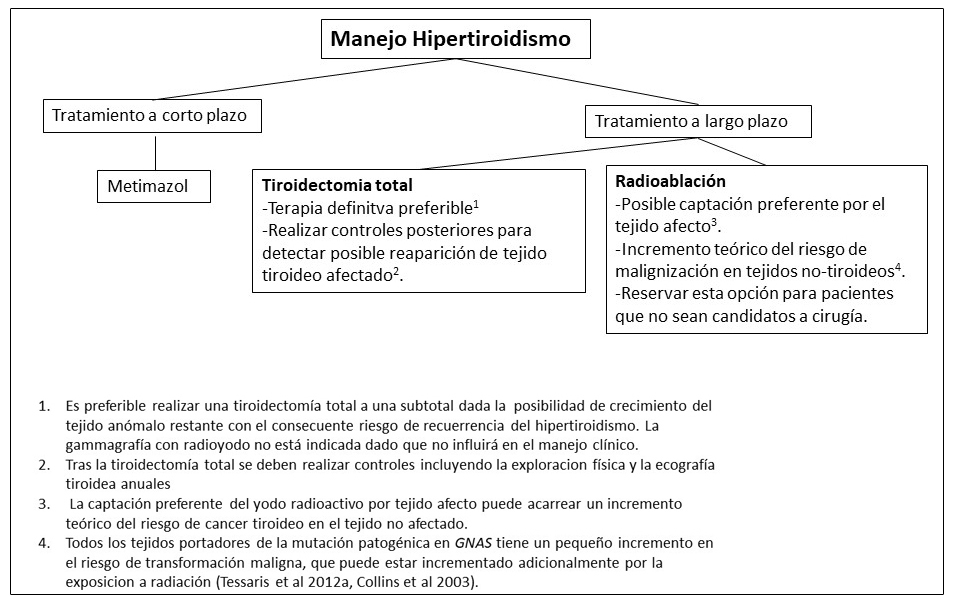

Tabla 4. Tratamiento de Endocrinopatías en individuos con Displasia Fibrosa/Síndrome de McCune-Albight

Figura 12. Manejo clínico recomendado para la pubertad precoz en niñas con Displasia Fibrosa/Síndrome de McCune-Albright

Figura 13. Manejo clínico recomendado para niños con alteraciones gonadales con Displasia Fibrosa/Síndrome de McCune-Albright

Figura 14. Recomendaciones para el manejo del hipertiroidismo en pacientes con Displasia Fibrosa/Síndrome de McCune-Albright

Figura 15. Recomendaciones para el manejo del exceso de hormona de crecimiento en pacientes con Displasia Fibrosa/Síndrome de McCune-Albright

Figura 16. Recomendaciones para el manejo del exceso del hipercortisolismo en pacientes con Displasia Fibrosa/Síndrome de McCune-Albright

Figura 17. Recomendaciones para el manejo de alteraciones pancreáticas en pacientes con Displasia Fibrosa/Síndrome de McCune-Albright